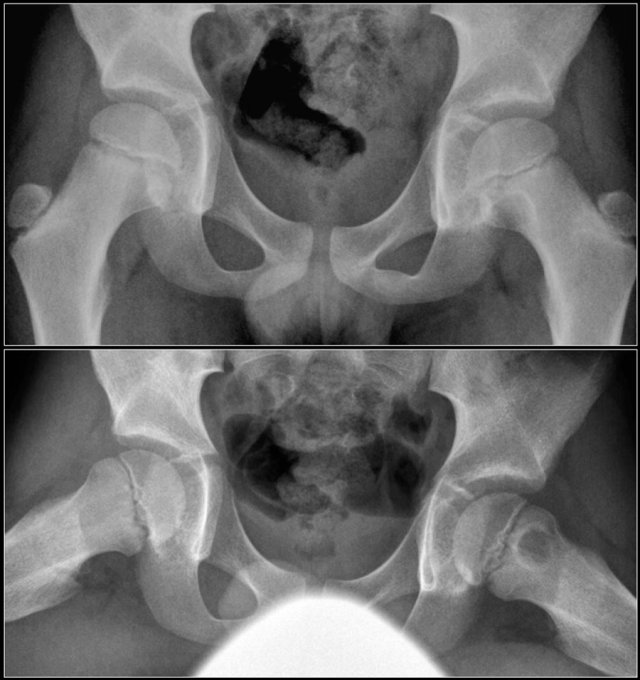

Avulsion injuries of the pelvis are a frequent cause of hip pain in adolescents involved in sports.

Because at this age the tendons are generally stronger than the apophyses, strong muscle contraction can result in apophyseal avulsion fractures.

Avulsion injuries can be acute or chronic.

Typical avulsion injury of the anterior inferior iliac spine at the insertion of the rectus femoris tendon.

Typical avulsion injury of the right ischial aphophysis.